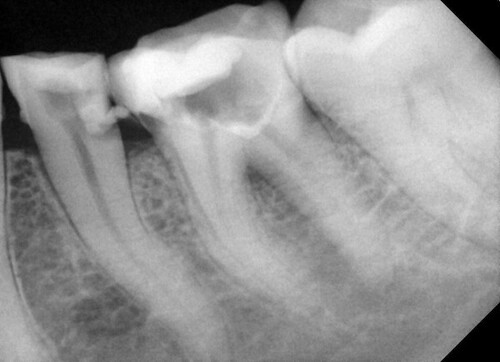

Формирование каналов проводилось с помощью никель-титанового файла (HyFlex™ CM, Coltene, coltene.com), а очистка проводилась с помощью 5,25% гипохлорита натрия и нормального физраствора. Каналы были расширены до 25/0,04 в мезиальных каналах (мезиобуккальном и мезиолингвальном) и 30/0,04 в одном дистальном канале. Небольшой кусочек синтетического коллагенового материала (CollaTape®, Zimmer Biomet Dental, zimmerbiometdental.com) был аккуратно уплотнен для создания барьера на уровне фуркации. Серый МТА (MTA Angelus® [Gray], Angelus, angelusdental.com) смешивался в соответствии с инструкциями производителя и укладывался на барьер CollaTape. В каналы были помещены гуттаперчевые точки, чтобы избежать попадания МТА в каналы (рис. 4).

Рис. 4